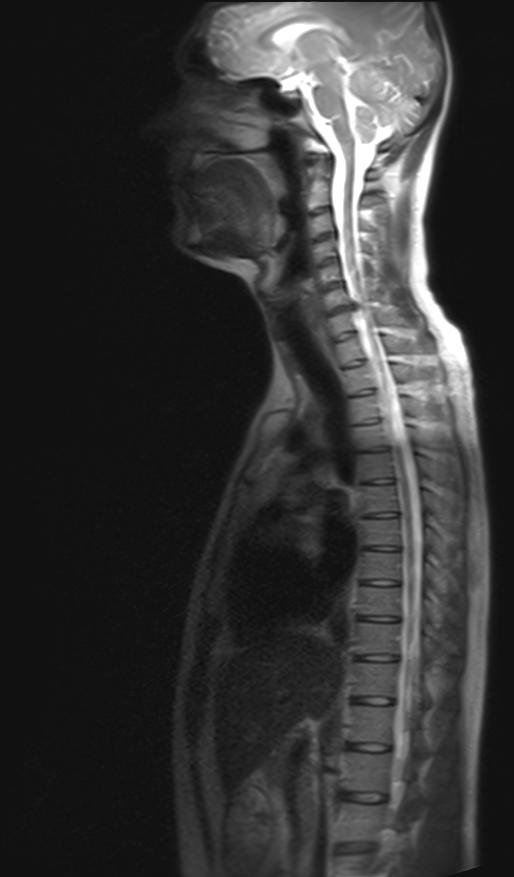

Entschlüsselung der MRT der Wirbelsäule ermöglicht es Ihnen, Läsionen in jeder seiner Säulen, Tumoren, Metastasen zu sehen. RADIOLOGIE)" as Want to Read - Der Wegweiser zu einer hochqualifizierten MRT-Diagnostik der Wirbelsäule und des Spinalkanals - Wann ist die MRT sinnvoll und was kann man von ihr erwarten? Spinal cord and spinal column tomography on MRI scan.

MRT oder Magnetresonanztomographie ist eine einzigartige, sichere Methode der Diagnose.